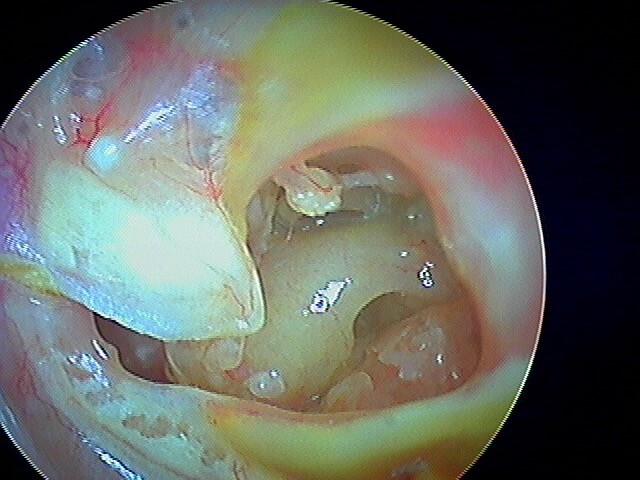

10/1 Cholestéatome acquis (secondaire)

Epithélium stratifié, kératinisé et squameux présent dans l’oreille moyenne, "croissance progressive de peau dans l’oreille", "skin in the wrong place": la peau malade du tympan va détruire tout sur son passage: le tympan lui-même, les osselets, le cadre osseux jusqu'à la méninge. Là il faut bien utiliser toutes ses connaissances sémiologiques d'otoscopie pour faire le diagnostic, qui est plus facile que l'otite atéléctasique, en raison de la présence de squames.

Le/la patient·e avait attendu quelques mois avant de revenir: le cholestéatome a englobé tout le malléus: